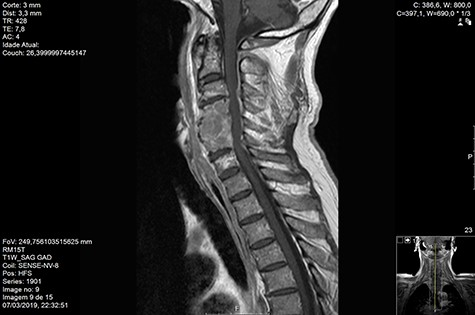

Computed tomography (CT) (Figs 1–3) and magnetic resonance imaging (MRI) (Figs 4–6) of the cervical spine were performed and revealed a lytic lesion involving most of C4, C5 and C6 vertebral bodies with bilateral extension to the posterior spinal elements of C4 and C5 and complete disruption of C4-C5 and C5-C6 intervertebral discs.

MRI and CT scans performed at 90 days post-radiation therapy showed an arrest of further progression of instability and resolution of the lytic lesion (Figs 7–13).